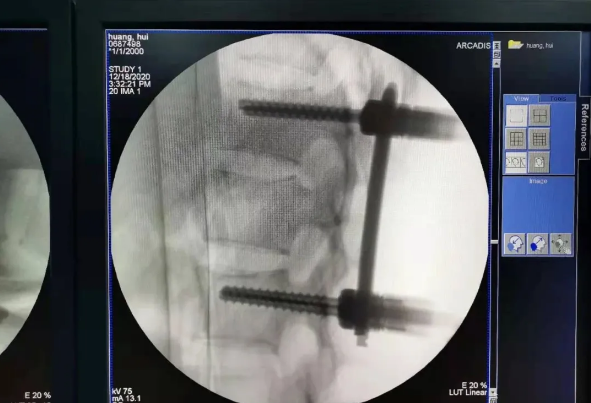

在传统骨科手术中,反复使用X线透视,有时须经常调整或更改手术固定方式,常常需要多年的临床经验积累,也难免意外频发,毕竟人眼判断和X线透视单平面观察的局限性是客观原因。

我国自主研发的天玑®骨科手术机器人,是针对骨骼硬组织的先进技术,已经获得国际认可,能够开展脊柱全节段 (颈椎、胸椎、腰椎、骶椎) 疾病、骨盆和四肢等骨折、骨肿瘤以及关节导航等手术。相比传统手术,机器人辅助手术具有手术创伤小、出血少、并发症少、康复快的优势。同时,由于不需通过反复透视来确定置钉位置,从而能减少术中辐射,大大降低患者辐射危害,且手术过程中,由机器人与主刀医师共同完成手术,大大增加了手术安全性。

在南昌市第一医院廖琦教授带领下,由创伤骨科团队借助天玑®骨科手术机器人为患者“量身定做”最理想、最安全的教科书般的通道,完美安全微创完成手术,并且手术时间明显缩短,真正做到“指哪儿打哪儿”!更让患者放心的是,天玑®骨科手术机器人的“稳定手”机械臂进行精准定位,不用反复探寻。

由于天玑®骨科手术机器人的精准及高效,可以使手术时间明显缩短,因此在骨盆骨折手术后,在廖琦教授指导下,脊柱外科团队利用天玑®骨科手术机器人同样为20岁女性腰椎骨折患者“量身定做”最理想、最安全的教科书般的通道,完美安全微创完成手术,手术不仅时间缩短,并且出血和透视减少。